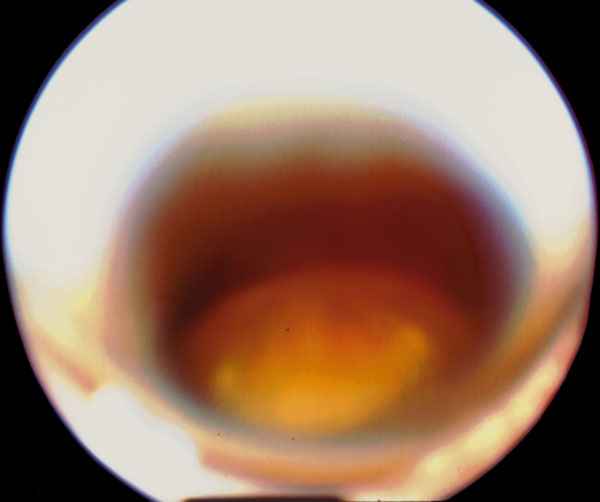

Figura 2

CRISTALINO LUXADO A CÁMARA VÍTREA SÓLO VISIBLE TRAS LA DILATACIÓN PUPILAR Y CON LA MIRADA DIRIGIDA HACIA ABAJO.